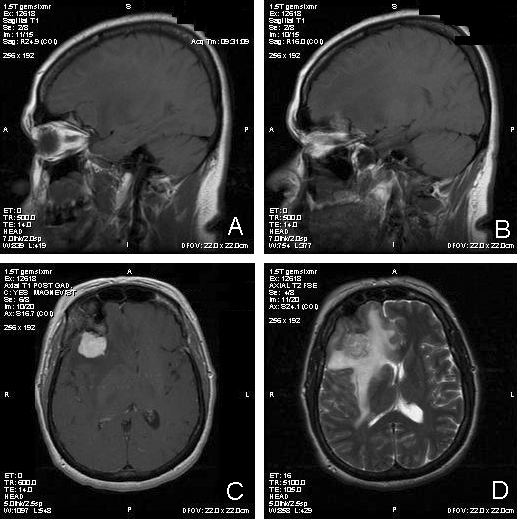

T1-weighed MR images demonstrate an extraaxial, dural based mass involving the right supraorbital region  (Panel A and B). The mass shows homogeneous enhancement  (Panel C). CT scan demonstrates as well as rim calcification (Panel E). On T2-weighed imagers, significant vasogenic edema is demonstrated despite the small size of the lesion and the extraaxial location (Panel D).